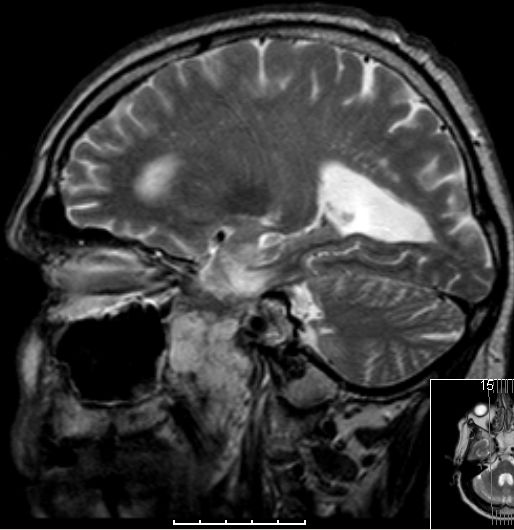

Glioblastome metastasieren normalerweise nicht außerhalb des ZNS. | |

| Fall | Im vorliegenden Fall kam es während der Temodal-Therapie nach postoperativer Radiochemotherapie zu einen Durchbruch des GBs durch die Schädelbasis. | |